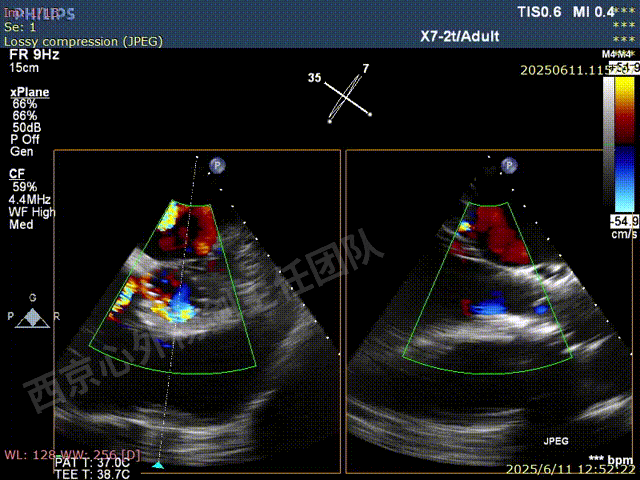

术前超声检查

TAVR术后,全心增大,二尖瓣反流重度,三尖瓣反流重度。中量心包积液。左室严重增大,标准图像调整困难。主动脉瓣位带支架人工瓣膜瓣叶启闭正常,主动脉瓣位人工瓣上血流速度Vmax 148cm/s,PGmax 9mmHg,Vmean 86cm/s,PGmean 2mmHg, VTI 34.7cm,瓣周反流(轻)。估测肺动脉收缩压约49mmHg;左室收缩功能明显减低。LVEF:23%,EDV:364ml,ESV:221ml。

彩色血流示:二尖瓣反流缩流颈彩宽6.6mm,面积17cm²,容积30ml;二尖瓣瓣口面积6.6cm²,瓣环内径:左右径34mm,前后径34mm。2区瓣叶长度:前叶36mm,后叶20mm,叶环比1.6. 三尖反流面积17.2cm²,容积33ml,Vmax 291cm/s,PGmax 34mmHg。